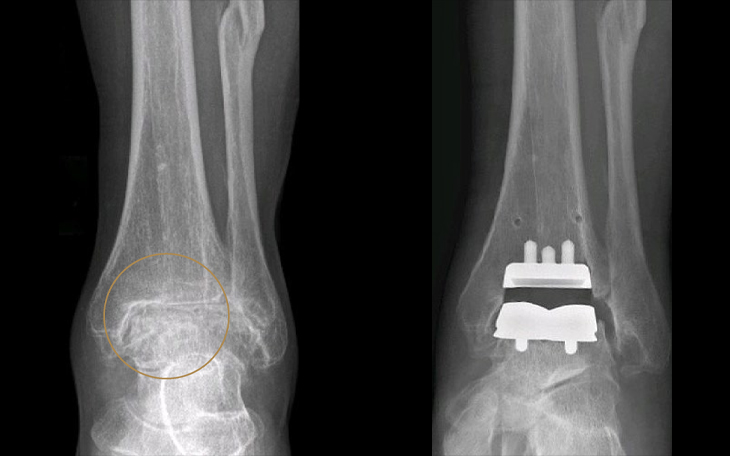

Links: Vollständiger Knorpelverlust mit Aufhebung des Gelenkspalts

Rechts: Postoperatives Bild nach Implantation der OSG-TEP

Wann wird Endoprothetik empfohlen?

Eine Endoprothese am Sprunggelenk wird empfohlen, wenn der Gelenkverschleiß (Arthrose) so weit fortgeschritten ist, dass konservative Maßnahmen wie Einlagen, Orthesen oder Infiltrationen keine ausreichende Schmerzlinderung mehr bieten. Typische Indikationen sind eine schwere Sprunggelenksarthrose nach Verletzungen oder Fehlstellungen.

Ablauf der Therapie

Vor dem Eingriff erfolgt eine umfassende Diagnostik mit DVT, Röntgen- oder CT-Aufnahmen und eine sorgfältige Operationsplanung. Bei der Operation wird das geschädigte Gelenk entfernt und durch eine passgenaue Prothese ersetzt, die eine möglichst natürliche Gelenkbewegung ermöglicht. Der Eingriff erfolgt in Voll- oder Regionalanästhesie. Nach der Operation beginnt eine gezielte physiotherapeutische Mobilisation, um Beweglichkeit und Belastbarkeit schrittweise aufzubauen.